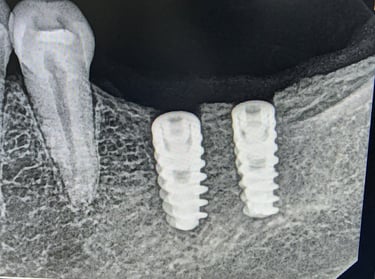

Screw retained implant crown

Dental implant surgery